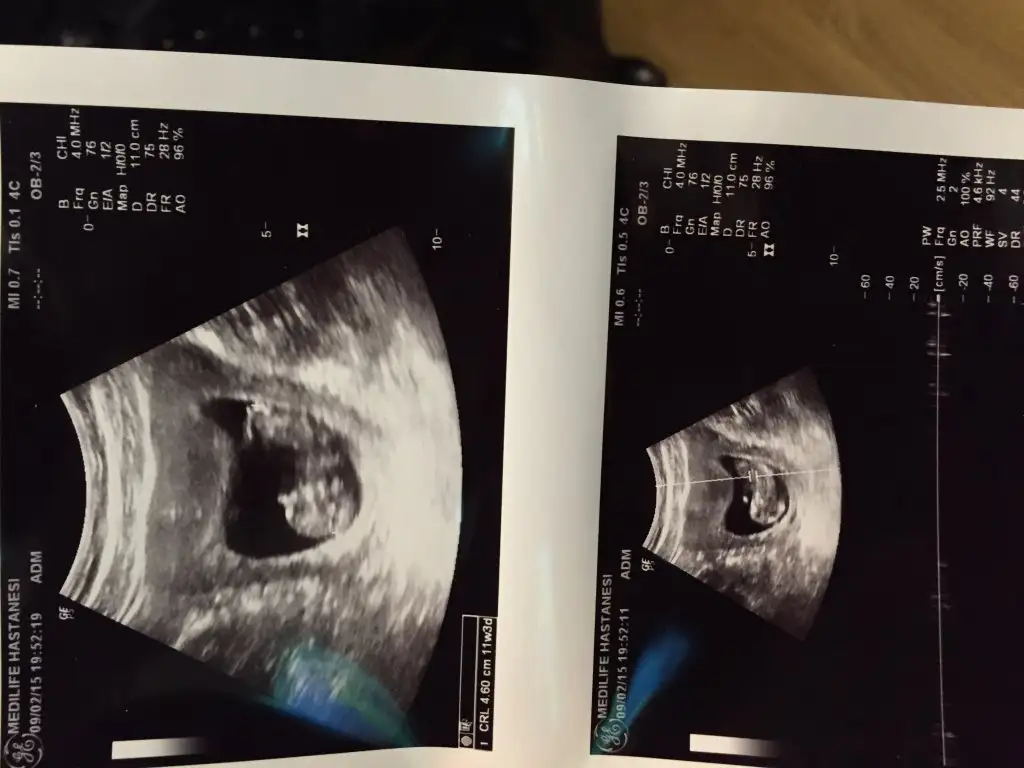

Kızlar merhaba şimdi dr dan çıktım. bu sefer kendi dr umum dışında başka dr a gittim. kendi dr umda kan tahlili yaptırmıştım fakat bana sorun yok demişti. tahlillerimi bugün gittiğim dr a gösterdim çok aşırı demir eksikliğin var dedi. ve kendi dr um idrar tahlili hiç istememişti bu dr istedi. cuma günü eksik olan tahlillerimi yaptırıcam ve ikili testi de tabii. bebeğim 4.6 cm olmuş :) ve tam haftasında maşallah. kalp atışlarını da ilk kez dinledim çok iyi dedi. fazla dinletmedi çok sağlıklı birsey değil bu dinletme olayı dedi. hergün 1 saat yürüyüş verdi. tansiyon ve kilo ölçümümü yaptı. demir eksikliği için ilaç verdi. folik asiti bırak artık bir işe yaramıyor bu saatten sonra dedi. benden havadisler bu şekilde

Eklentiler

• image.webp

image.webp

31,9 KB · Görüntüleme: 117